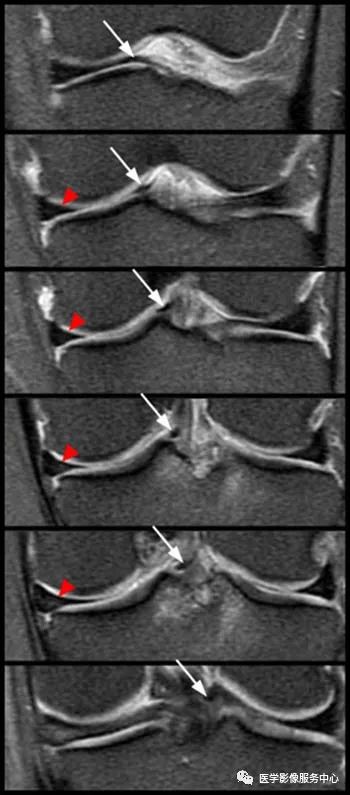

从前到后的连续冠状位脂肪抑制质子密度加权图像显示了内侧斜行韧带走行过程,从内侧半月板的前角到外侧半月板的后角。(红色箭头为正常的半月板 )(白色箭头为正常走行的斜行韧带)

尽管斜行板间韧带可以模仿桶柄撕裂影像表现,但其在交叉韧带之间走行可以将其与翻转的桶柄撕裂区分开来,特别是在半月板形态正常的情况下更能区别桶柄状撕裂。